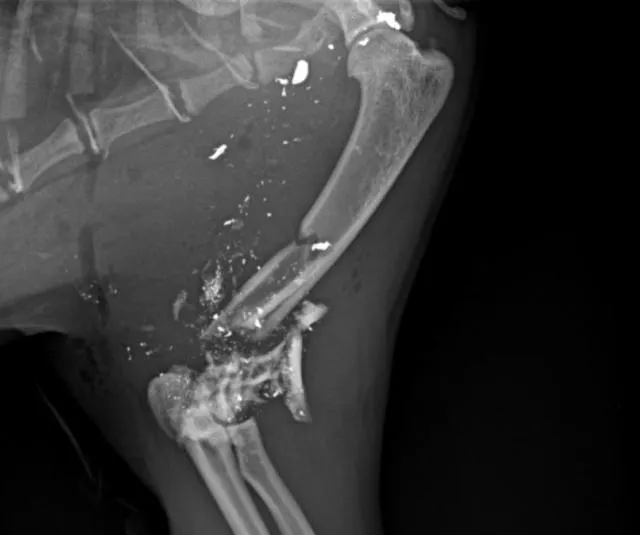

Le vétérinaire fait passer une radio à Jack. « Quand il est revenu, il nous a dit que notre chat s’était pris une balle. Qu’on lui avait tiré dessus. L’intérieur de la patte est complètement explosé. Les taches blanches que l’on voit sur la radio, ce sont des fragments de balle. On va essayer d’en récupérer pour les apporter à la police. »

Sur la radio prise par le vétérinaire, on voit des taches blanches, qui sont en fait des extraits de balle. Clinique Anovet